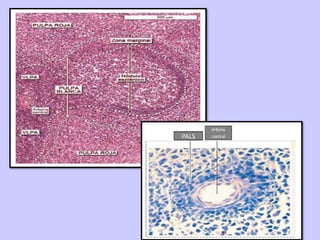

ORGANIZACIÓN

HISTOLÓGICA

• Pulpa blanca

– Tejido linfoide difuso y

nodular

– Áreas grises de 0.2 a 0.7

mm diámetro

• Pulpa roja:

– Senos venosos

– Cordones esplénicos (de

Billroth)

– Abundantes eritrocitos

(color rojo) en senos y

cordones esplénicos

• Las relaciones entra

las pulpas roja y

blanca dependen de

la distribución de

vasos sanguíneos:

– La blanca se encuentra

alrededor de las

arterias

– La roja rellena los

intersticios entre los

senos venosos

• Forma vainas linfoides

periarteriales (VLPA),

con algunos centros

germinales

• Las Vainas Linfoides

Periarteriales siguen a

los vasos sanguíneos

hasta que se ramifican

en capilares.

PULPA BLANCA

En las vainas predominan los

linfocitos T del contingente

recirculante

Los centros germinales tienen

principalmente linfocitos B

• Responde a antígenos

transportados por sangre.

• En las Vainas Linfoides

Periarteriales aparecen:

–Linfocitos grandes

–Linfoblastos

–Células plasmáticas inmaduras

ZONA MARGINAL

• Periférica a las

Vainas Linfoides

Periarteriales

• Entre pulpa roja y

blanca

• Mide de 80 a 100

um

• Entramado denso

de fibras

reticulares, con:

– Pequeños linfocitos

– Células plasmáticas

•La zona marginal recibe la

sangre arterial que llega a

la pulpa roja.